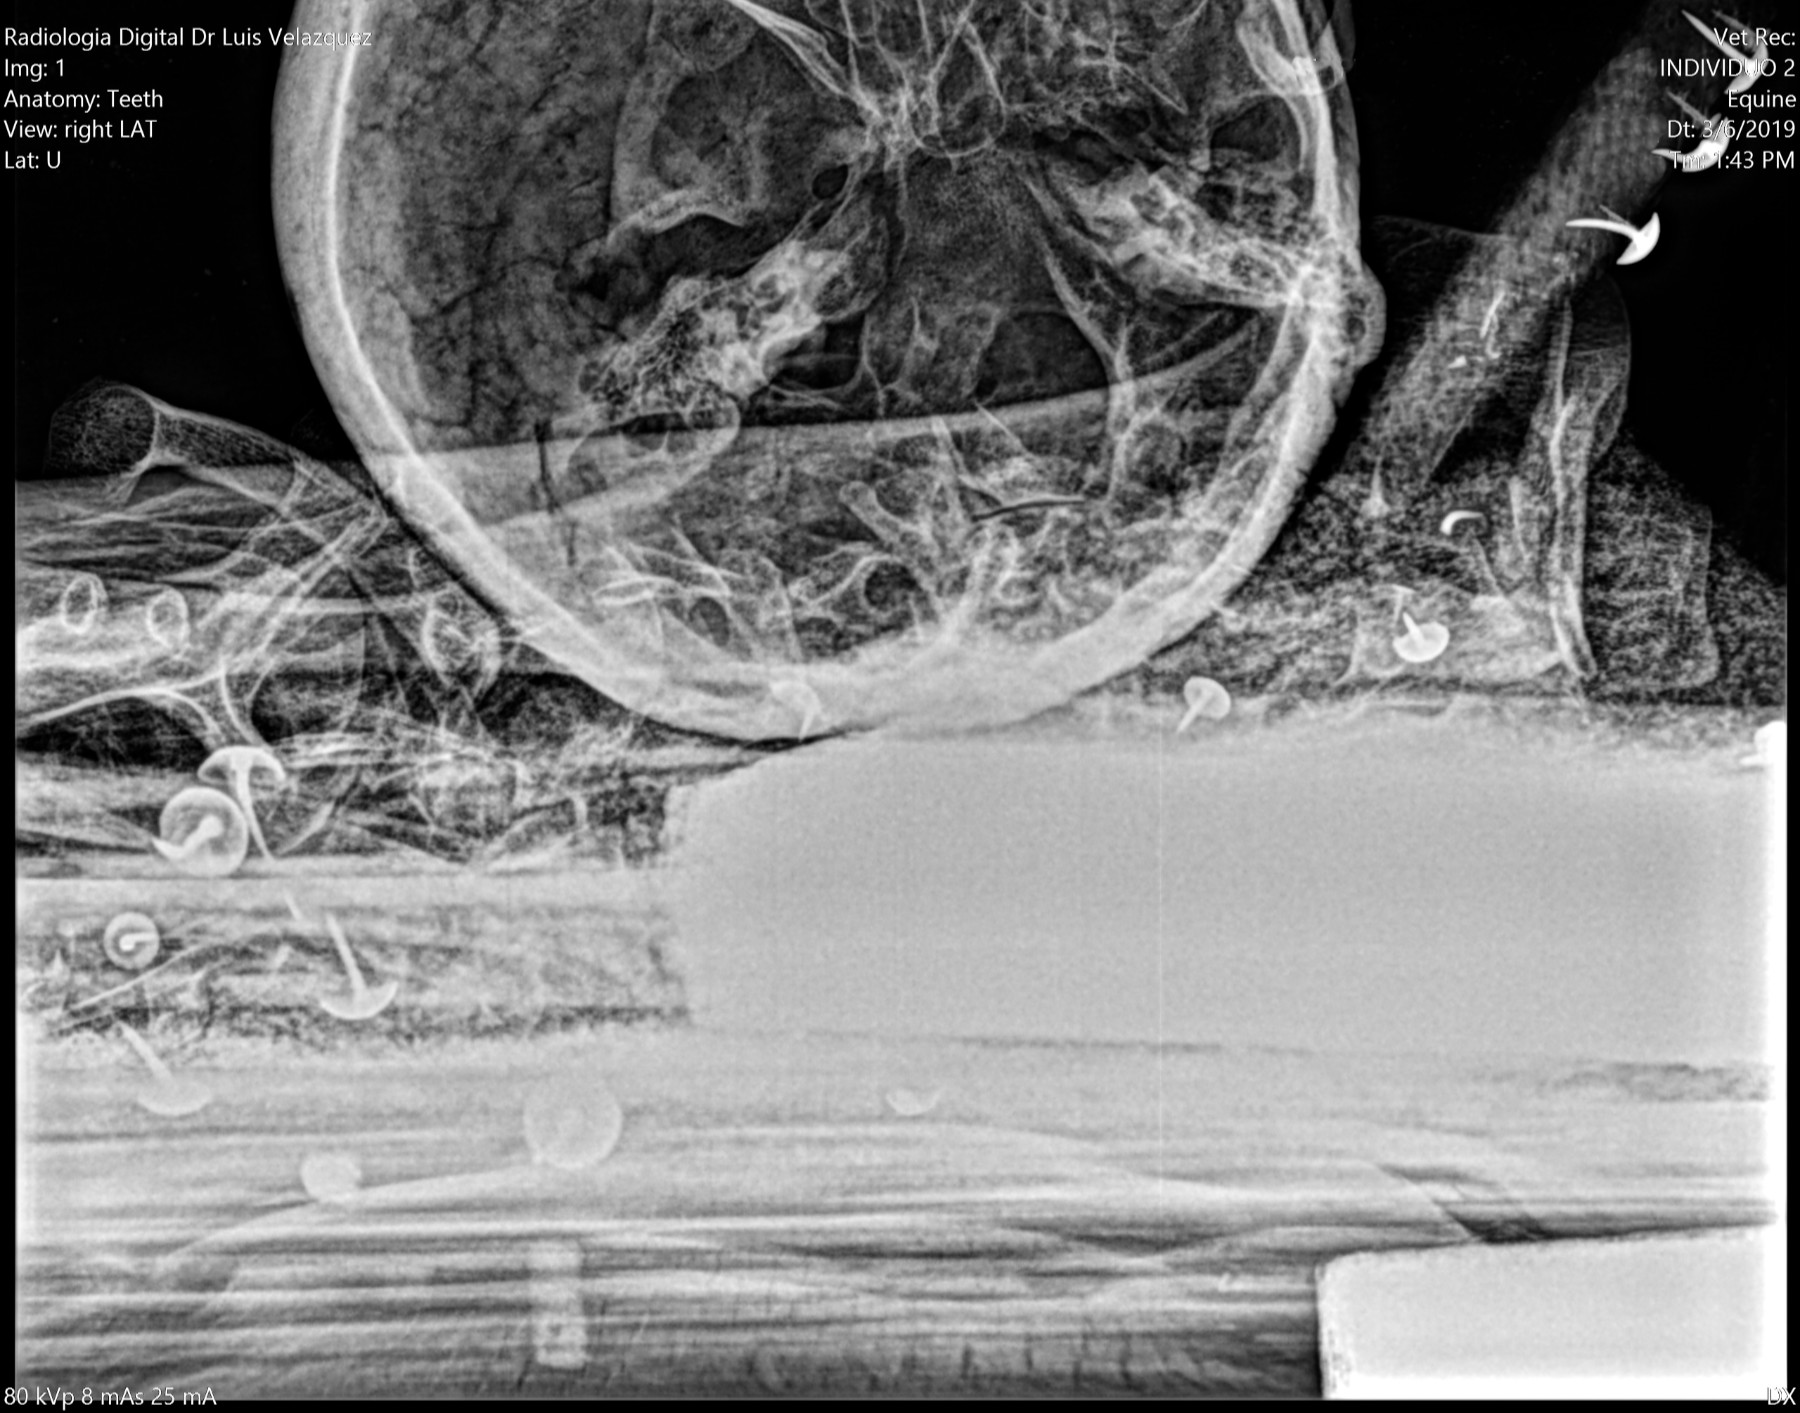

Radiología Digital como Herramienta Complementaria en el Dictamen de Bienes Muebles